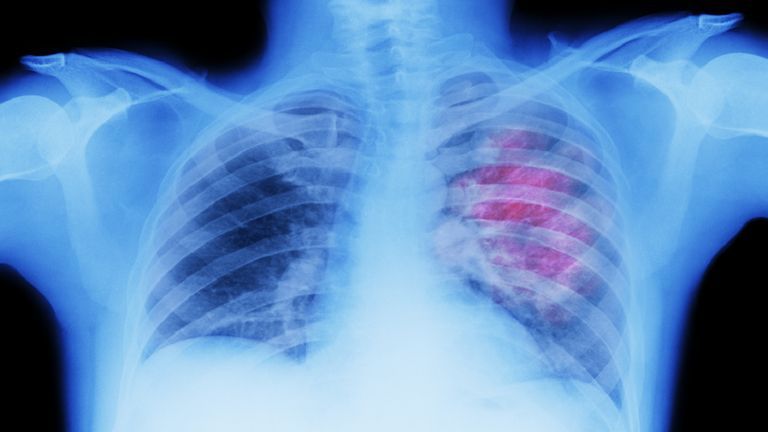

ولفت الاستشاري إلى أن أخطر المراحل هي التي تحدث بعد التعرض للغاز بتركيز عالٍ أو لفترة طويلة نسبياً: “الضرر الأكبر يكمن في إمكانية حدوث الوذمة الرئوية (الاستسقاء الرئوي)، حيث تتجمع السوائل في الرئتين. هذا يمنع تبادل الأكسجين بشكل فعال، وقد يؤدي إلى تدمير جزئي أو كلي للقصبات الهوائية والأسناخ، الأمر الذي يضع المصاب في خطر الفشل التنفسي ويهدد حياته على الفور”.

* طلب الرعاية الطبية: “يجب نقل جميع المصابين، حتى أولئك الذين تبدو أعراضهم خفيفة، إلى المستشفى. الوذمة الرئوية قد تتأخر في الظهور لساعات، ولهذا يجب وضعهم تحت المراقبة المكثفة للحصول على دعم الأكسجين وتقييم الرئتين عبر الفحوصات المتخصصة”.